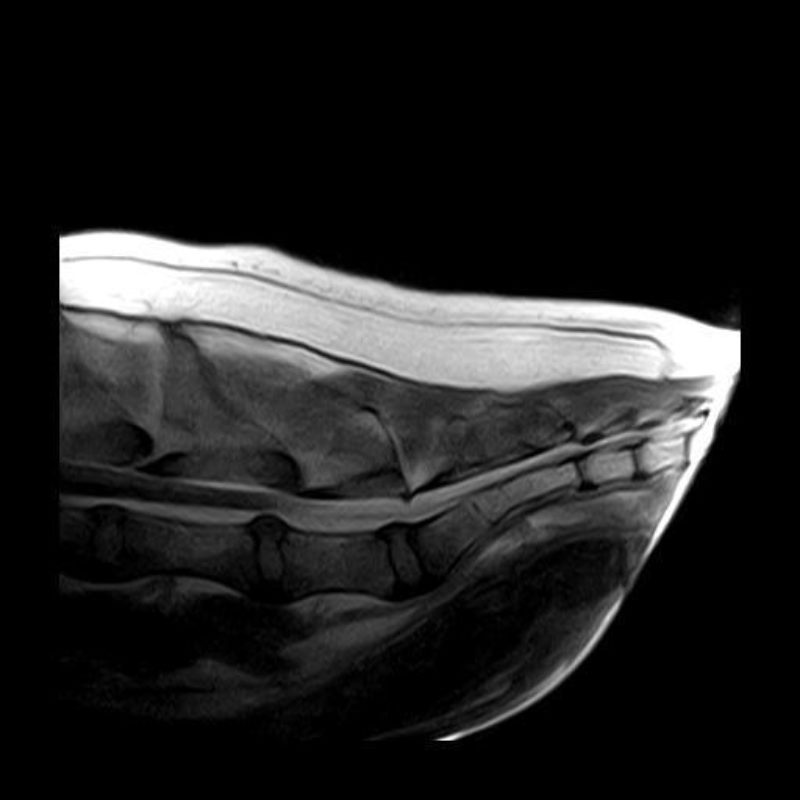

Das „A und O“ jeder Therapie ist die Gewissenhaftigkeit der Diagnostik. Sie fängt bereits bei der Vorberichtserhebung an. Ausführliche Gangbildanalysen und Schmerzpunkt-Untersuchungen sind genauso unerlässlich wie der Einsatz geeigneter, bildgebender Verfahren wie auch bei Bedarf Labordiagnostik. Hier müssen wir entscheiden, ob man Röntgenbilder anfertigt, Ultraschalldiagnostik betreibt, oder sogar CT- oder MRT-Aufnahmen benötigt. Herz und Kreislauf werden auf Narkosefähigkeit geprüft. Sobald man sich vor dem Hintergrund mittlerweile jahrzehntelanger Erfahrung für die Methode der Goldakupunktur entscheidet, kommt das Spezialwissen der Traditionellen Chinesischen Medizin und der Akupunktur auf den Plan. Auf Basis der westlich-wissenschaftlichen Erkenntnisse um Schmerz und Biomechanik auch unter Zuhilfenahme verschiedener z.B. pulsdiagnostischer Verfahren wird der der Akupunktur-Kontext ermittelt. Daraufhin wird ein Implantationsprotokoll. Dieses bezieht auch unter Umständen weitere, bestehende Leiden mit ein, wie z.B. Anfallsleiden, innere Erkrankungen, neurologische Erkrankungen oder Funktionsstörungen wie Inkontinenz.

Die Goldakupunktur ist wie jede andere Therapieart kein „Alleskönner“! Sie hat sich aber seit Jahrzehnten als Schmerztherapie bei folgenden Krankheiten bewährt: Hüftgelenksdysplasie, Hüftgelenksarthrosen, Arthrosen der Ellenbögen, Schultergelenke, Kniegelenke, Sprunggelenke, Vorderfußwurzelgelenke wie der Zehengelenke, bei Wirbelsäulenleiden bis hin zu neurologischen Begleiterkrankungen wie z.B. auch dem Cauda Equina Compressions Syndrom. Häufig können wir erreichen, dass die meisten Patienten über lange Zeit frei von Schmerzmitteln bei guter Lebensqualität aktiv am Leben teilnehmen können.